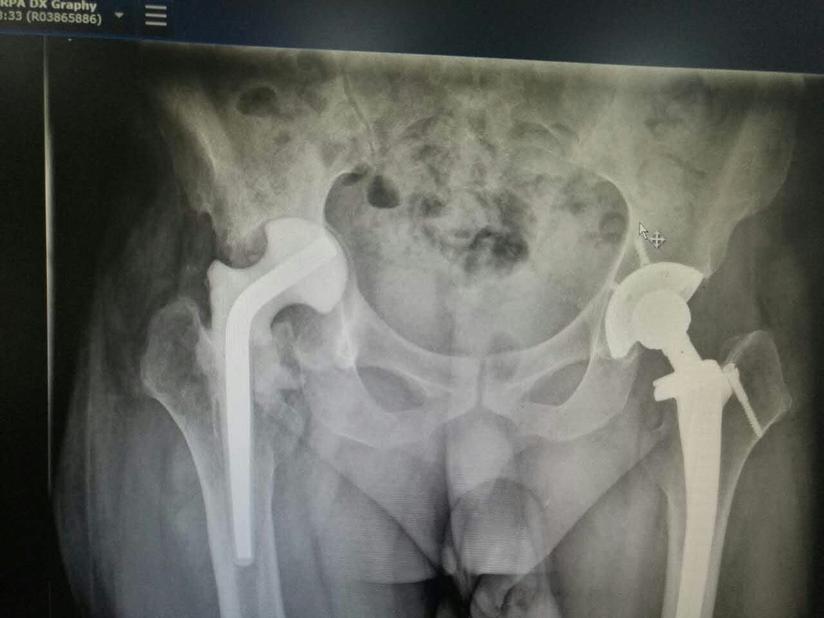

栖霞市人民医院骨外科为96岁高龄老人成功实施人工髋关节置换术 健康科普 栖霞市人民医院